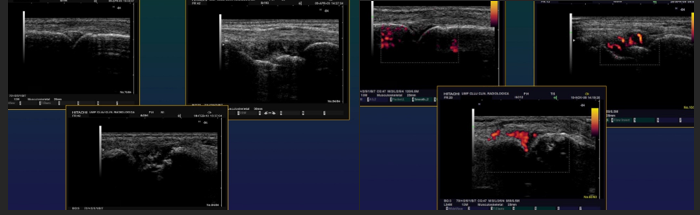

Septic Arthritis US

Small fluid effusions

Thickened synovial membrane + Doppler signal in acute phase

US guided joint punctures (Dg, therapeutic)

RA US

Small fluid effusion of joints

Panus

Erosions

Rheumatoid nodules